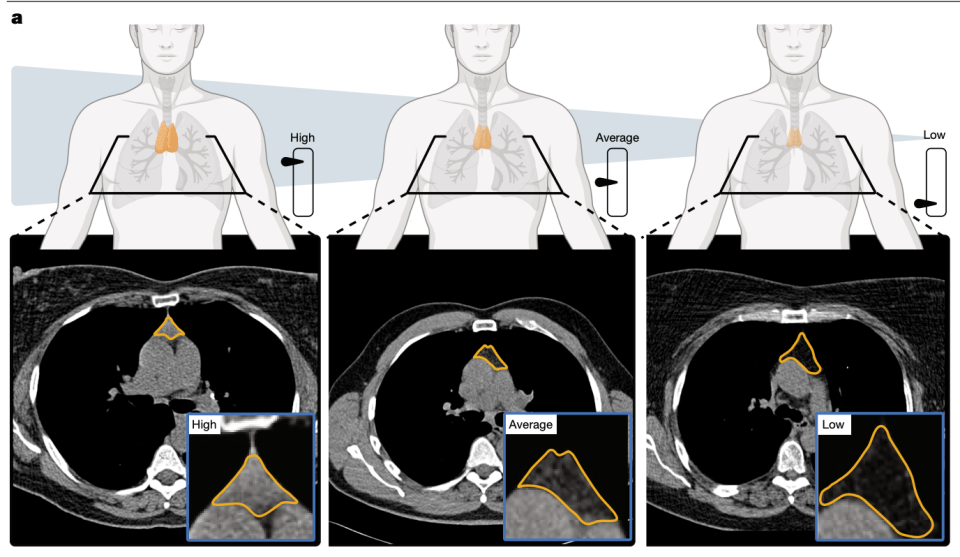

研究团队先利用5674例胸部CT数据训练深度学习模型,该模型能自动识别胸腔内的胸腺床位置,排除脂肪组织干扰,提取胸腺组织的影像学特征,最终生成0-100分的胸腺健康评分——0分代表胸腺完全脂肪化、丧失功能,100分代表胸腺功能完好。

AI通过CT影像自动识别胸腺位置并提取影像特征,最终输出0–100分的胸腺健康评分,实现无创量化评估。